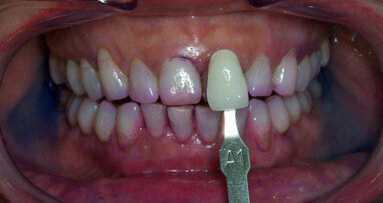

Case report Un paziente di anni 29 di sesso maschile si presenta per un controllo. In apparente salute sistemica, riferisce di avere bisogno di mostrare un sorriso luminoso e bianco poiché, essendo un odontoiatra, ha deciso di dedicarsi alla pratica clinica quasi esclusivamente estetica e cosmestica, comprese le tecniche di antiagening periorali (fotoringiovanimento e filler), e vuole valorizzare nei confronti dei suoi pazienti il suo aspetto curato e il sorriso smagliante, a mo’ di modello per corretti stili di salute orale; essere quindi testimonial esso stesso dell’efficacia delle terapie proposte.